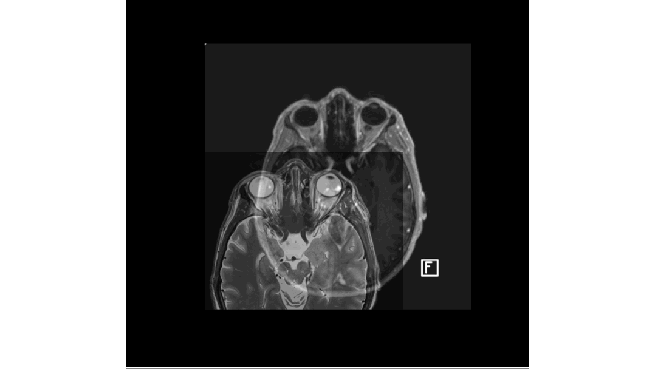

- מידת הבהירות בה ניתן להבחין באזורי המטרה (לראות לאן המנתח צריך להגיע עם האלקטרודה) בצילומי המוח הקודמים לניתוח – ישנן מטרות DBS, לחולי פרקינסון, שלא ניתן להבחין בהן כלל ב MRI של המוח.

שוק ה DBS גדול וחברות המכשור הרפואי הגדולות בעולם עוסקות בתחום באינטנסיביות. SIS מנסה לפתור את הבעיה השניה ברשימה – הנחת העבודה היא שאם הצוות הרפואי יראה בבירור את המטרות, יהיה קל יותר לתכנן את הניווט למטרה ולנווט בפועל, לפיכך SIS מייצרת מיפוי מדויק והצגה ברורה של מטרות ה DBS עבור פרקינסון. התקווה היא שכתוצאה מכך אחוזי ההצלחה של הניתוחים יעלו, התועלת לחולים תגדל והשימוש בטכנולוגית DBS יגבר.

בצילומי מוח באמצעות מכשירי הדמיה של 7 טסלה ניתן לראות פרטים, כמו מטרות DBS של ניתוחי פרקינסון, שאינם נראים במכשירי 1.5 ו 3 טסלה (מכונים גם מכשירי MRI קליניים). בהינתן תמונות מוח של אותו חולה, ב 7 טסלה ו 1.5 טסלה – ניתן יהיה ללמד את המחשב ״למצוא״ את המטרות, שנראות בברור בתמונת ה 7T, גם בתמונה הקלינית.

השנתיים הראשונות הוקדשו לחיבור כל המרכיבים לכדי מוצר תוכנה שלם וביסוס הפלטפורמה בענן. אט אט, הרעיון הפך למוצר הקולט צילומי MRI (שנעשים לפני הניתוח) ו CT (אחרי הניתוח, כשהאלקטרודה כבר בתוך בראש…), מנבא את אזורי המטרה לפני הניתוח ומראה מה קרה בפועל לאחר הניתוח. כמה מדויק מוקמה האלקטרודה ביחס למטרה.

דוקא בתקופת הקורונה, כשכל אחד בביתו, הושלם המהפך המוצרי המשמעותי. אפשט ככל שניתן – מכיוון שהבעיה ש SIS מנסה לפתור היא בעית סגמנטציה, לזהות מה בתמונת ה MRI של המוח הוא מטרת פרקינסון לניתוחי DBS, צמצמנו למינימום שימוש ברגיסטרציה ועברנו לשימוש במודלים של Deep Learning המיועדים לבעיות סגמנטציה. בפשטות – לימדנו את המחשב לזהות מטרות DBS לניתוחי פרקינסון. היתרונות עצומים – המוצר הפך פשוט בהרבה, זרקנו המון קוד ישן (כיף אדיר), הורדנו את זמן הריצה משעות לדקות בודדות ושיפרנו את הדיוק של המערכת (כי בכל רגיסטרציה יש טעויות ולכן ריבוי רגיסטרציות = ריבוי טעויות). על הדרך אפשר היה להוסיף את מטרת ה DBS השניה לפרקינסון, משום שמודל שיודע למפות מטרה אחת בתמונה, יידע בסבירות גבוהה ועם הדאטה המתאים, למפות גם מטרה אחרת.